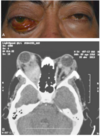

Estudios de imagen para valorar orbita

RM , TC y USG

Prueba dx en oftalmopatía tiroidea

TC (músculos engrosados)

Estudio de imagen para seudotumor

Tc (mejor) o USG modo A y B